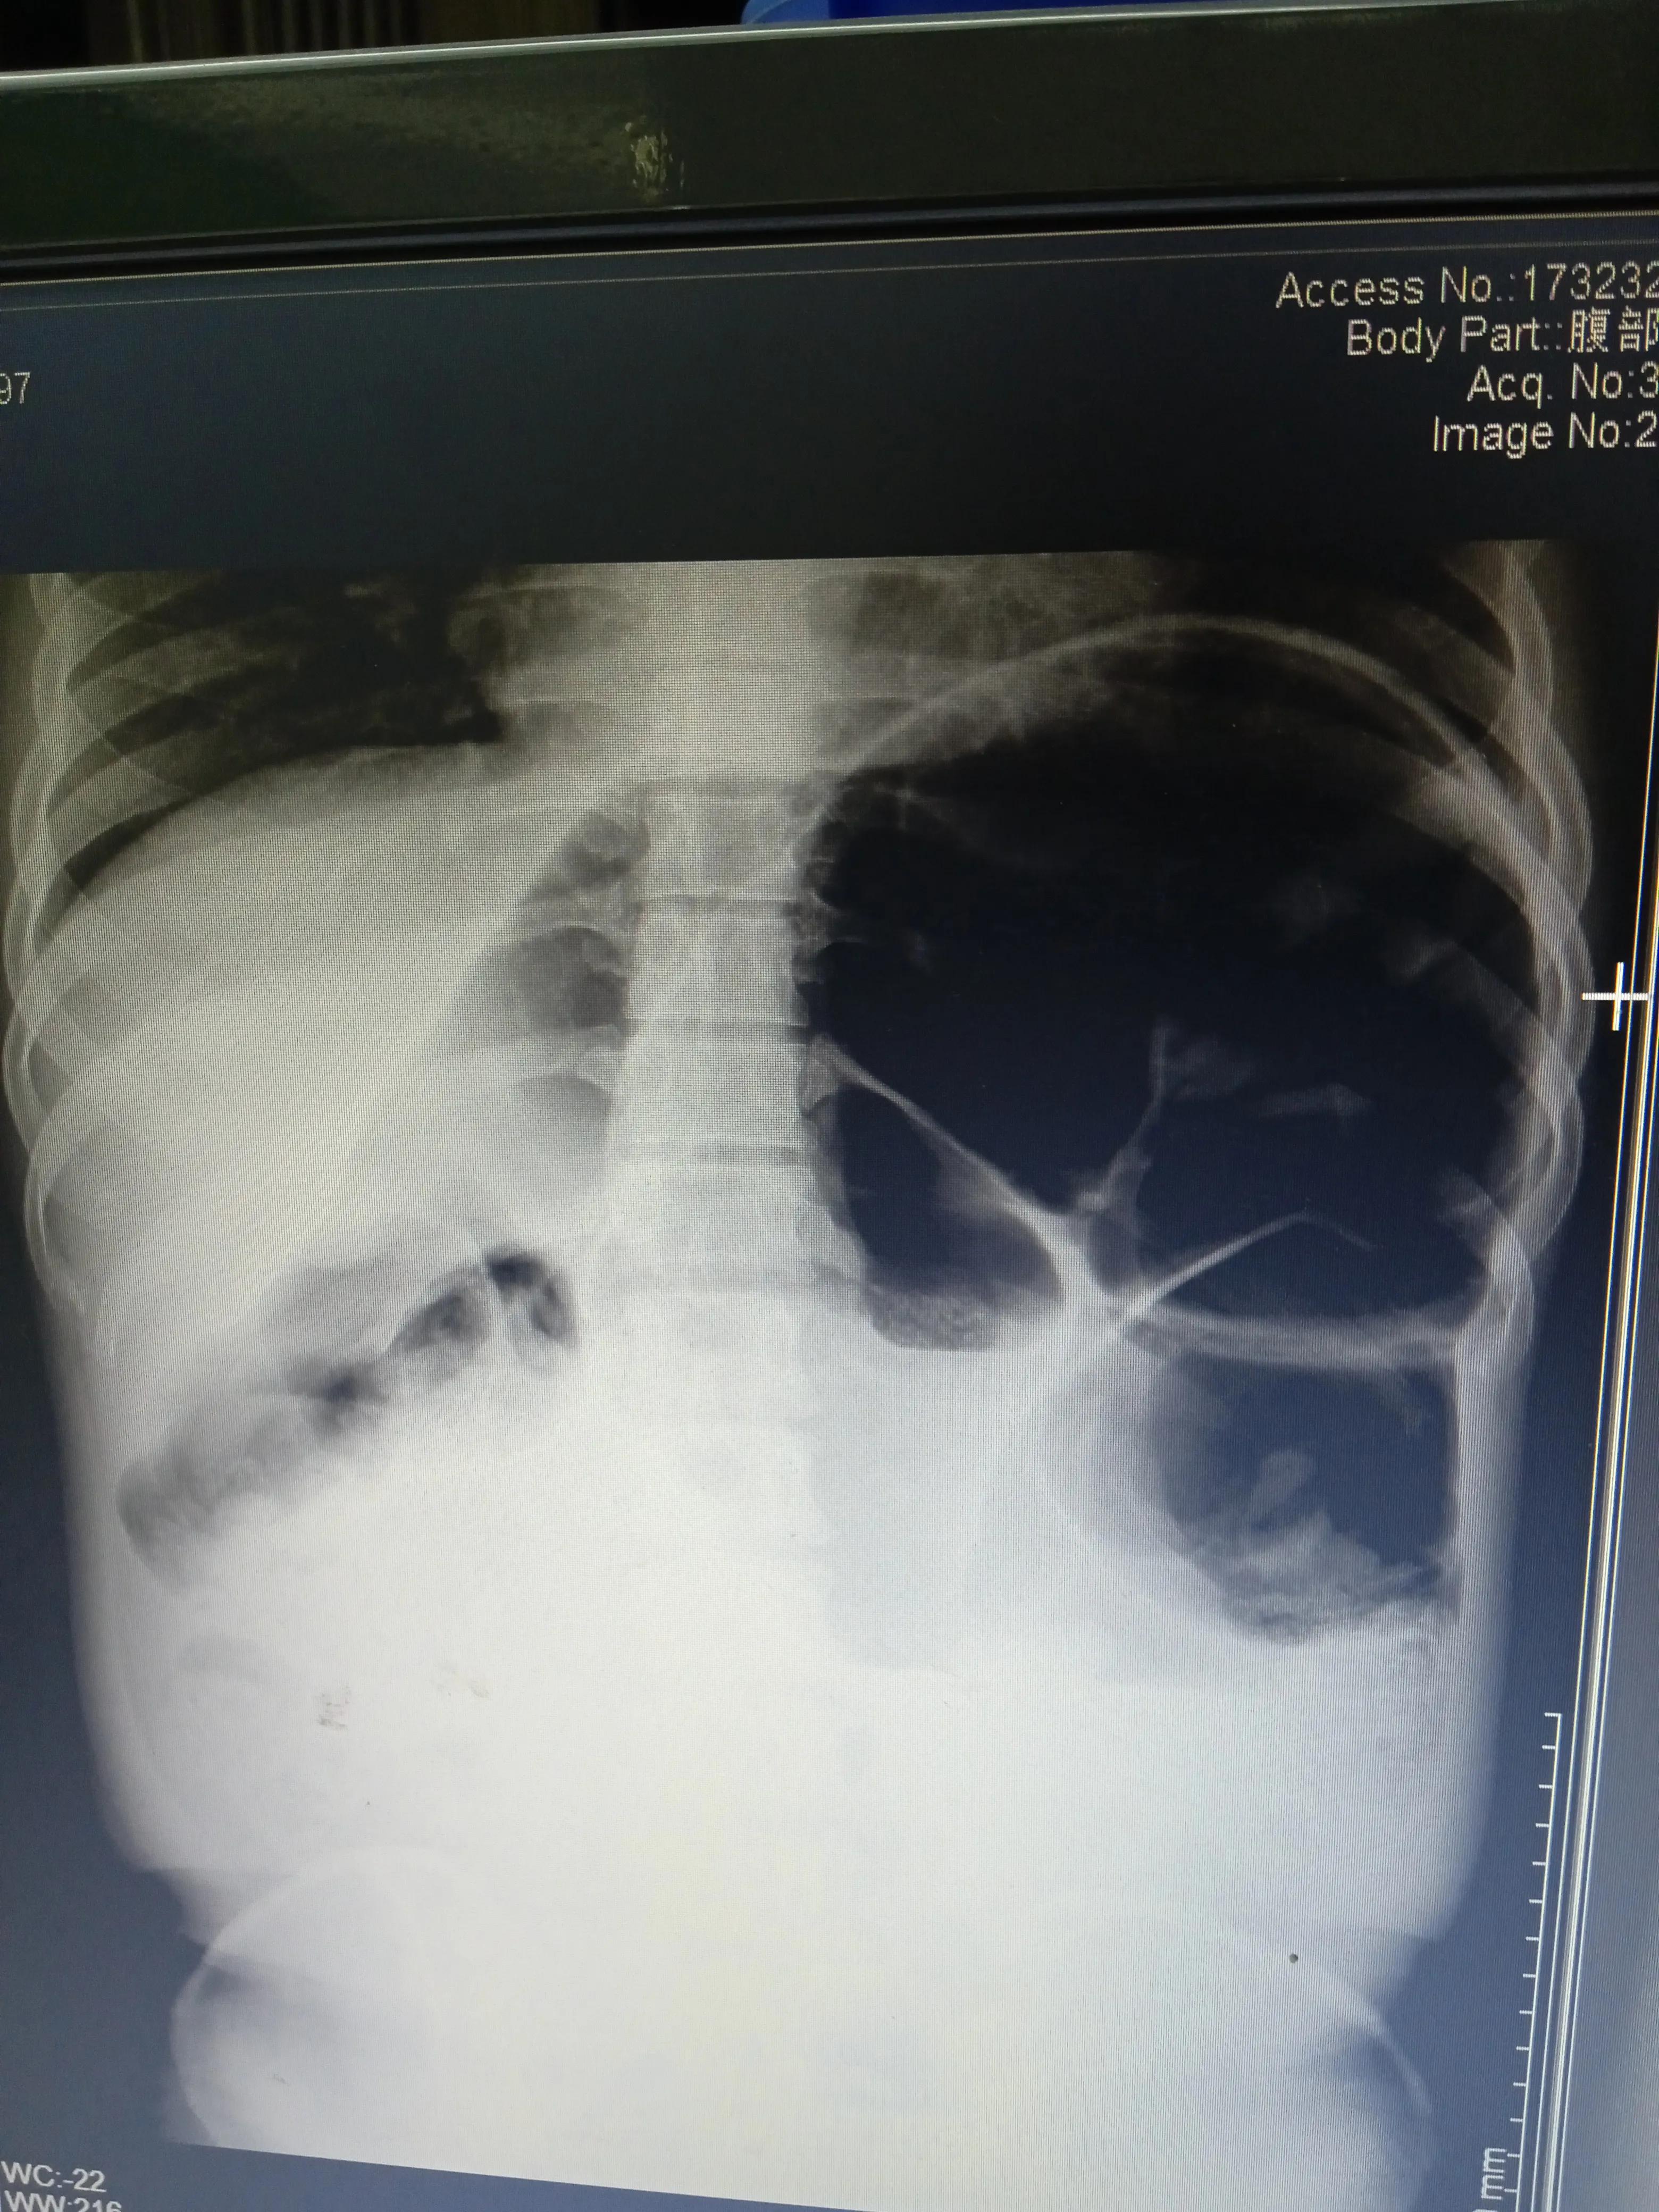

接诊时:腹部膨隆,左上腹压痛及反跳痛明显,肠鸣音亢进,有9次/分钟,闻及气过水声。

询问病史郭大娘“胀”“吐”“痛”“闭”四大典型肠梗阻症状都有了,加上便秘。高度考虑宿便引起肠梗阻。

后来拍腹部立位平片:左中上腹见多发肠管扩张及液平,提示肠梗阻。